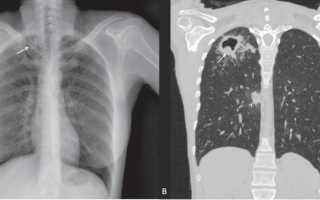

Снимки туберкулеза легких после операции

• диссеминированный плеврит — множественные очаги поражения по всему лёгкому. Имеют чёткие края и не сливаются друг с другом, диаметр около двух-трёх миллиметров, могут обнаруживаться одновременно в нескольких долях лёгкого. image Синдром уплотнения. Очаг низкой и средней плотности. Туберкулез.